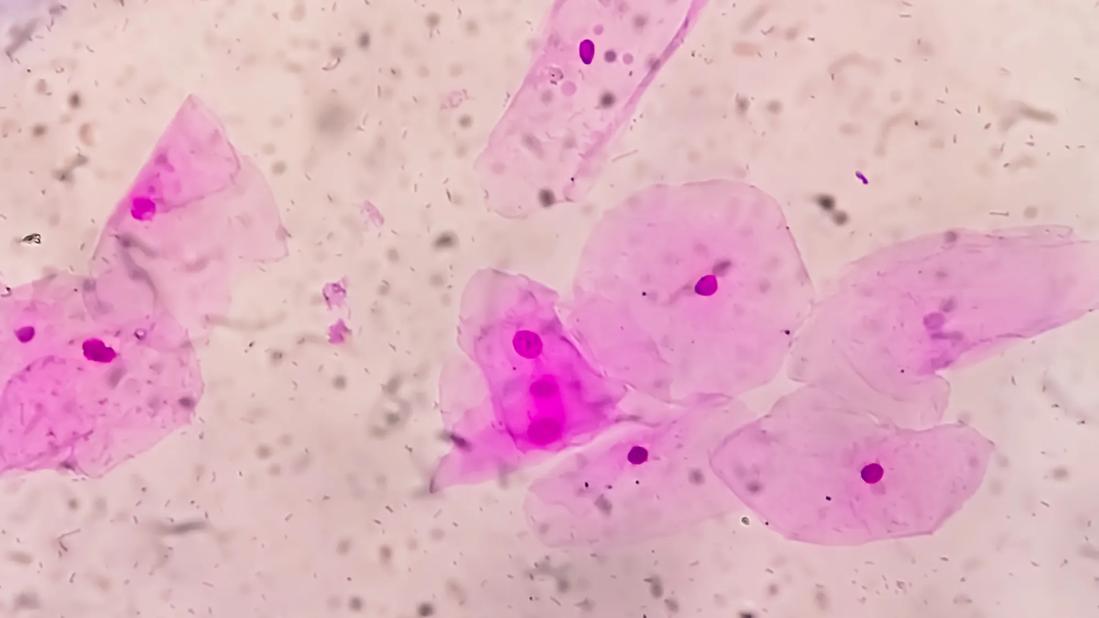

Slide image of bacterial vaginosis